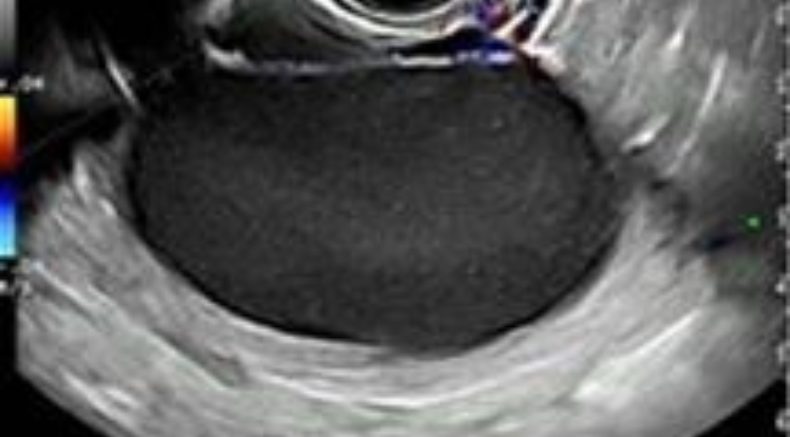

Typically an endometrioma is a cyst with 1 to 4 locules and a low-level echogenicity representing old blood in the cyst cavity (commonly termed ‘ground glass’) with no or sparse vascularization in the cyst capsule at ColorDoppler evaluation 8 without any papillary proliferations and with a clear demarcation from the ovarian parenchyma.

Endometriomas may also have ‘atypical’ features (in a minority of reports): multilocular (with more then 4 locules) ground glass masses with no internal flow, cysts with heterogeneous echogenicity of the cyst content, with internal calcifications or anechoic cysts, and frequently debris within the cyst may give the impression that it is a unilocular-solid lesion with solid papillary projections.